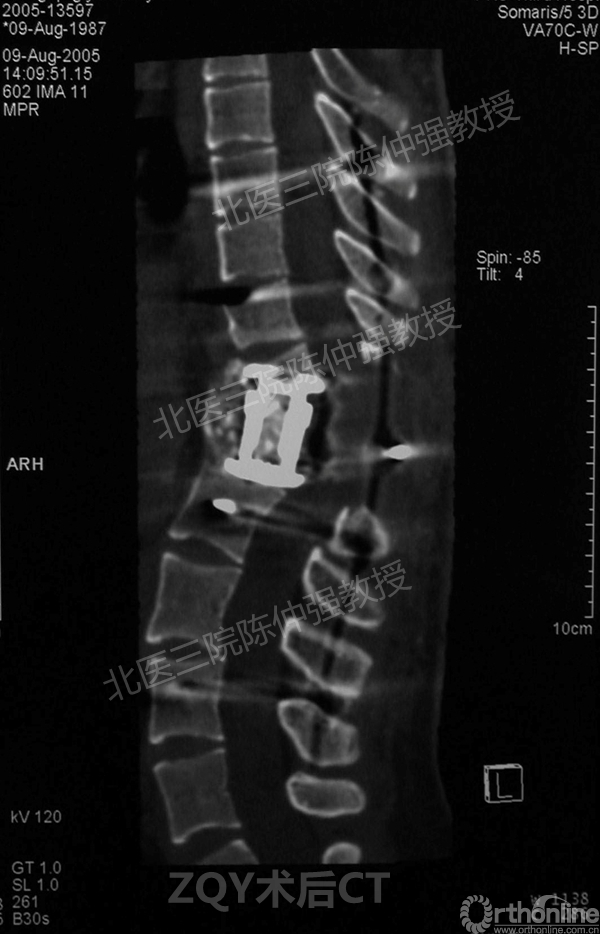

ZQY术后半年

患者女性17岁,胸腰椎陈旧结核性侧后凸畸形,局部呈“麻花状”扭转,无神经功能受损表现。2005年,陈仲强教授带领团队实施后路+侧前方联合入路脊柱节段切除、双轴旋转矫形术。术后患者外观显著改善,神经功能正常。术后随访证实患者截骨矫形节段骨性融合良好,矫形效果持续良好。